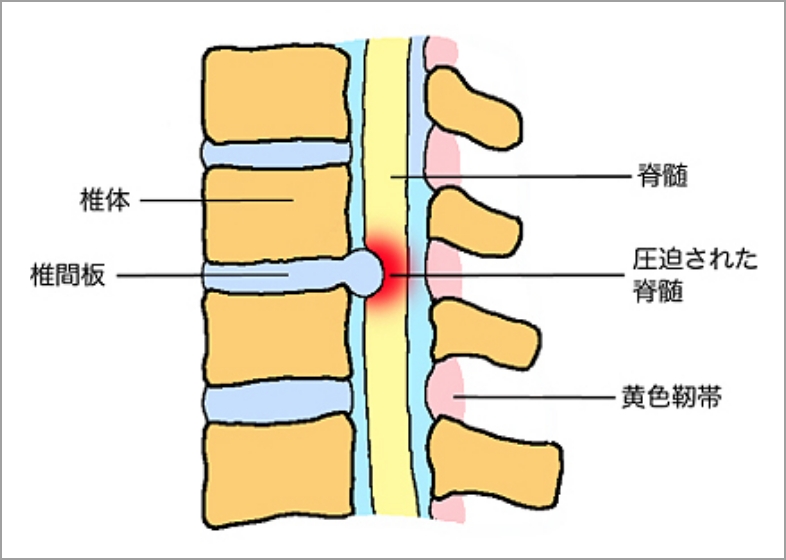

椎体の間に存在し、衝撃を吸収する役割を担っている軟骨組織が椎間板です。突然の外力や長期間の腰部に蓄積された負担により、椎間板の周囲を構成している線維輪と呼ばれる組織に裂隙が生じ、内部の髄核と呼ばれる組織が後方に突出、脱出する事で疼痛が出現します。突出した髄核が神経組織を圧迫すると、腰部、下肢への疼痛、しびれ感などの症状が出現します。症状が軽度である場合には、投薬、安静(外固定を含め)、牽引などによる治療が行われますが、四肢・手足の麻痺、排尿・排便の障害、耐えられない疼痛、しびれ感などを認めた場合には、可及的早期の外科治療が必要となります。